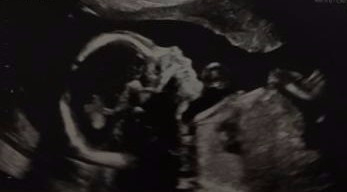

Kyle and I just had our 20 week ultrasound and it was such a thrill to see her!  The doctor said she is 13 ounces right now, standard is 10 at the 20 week mark; so she is growing well! She was moving the whole time during the ultrasound and grooving to her own beat womb-style. She was in a breach “pike” position which made it hard for the tech to take photos, but we got everything that was needed and a clean bill of health reported. Happy Momma and Poppa to be!